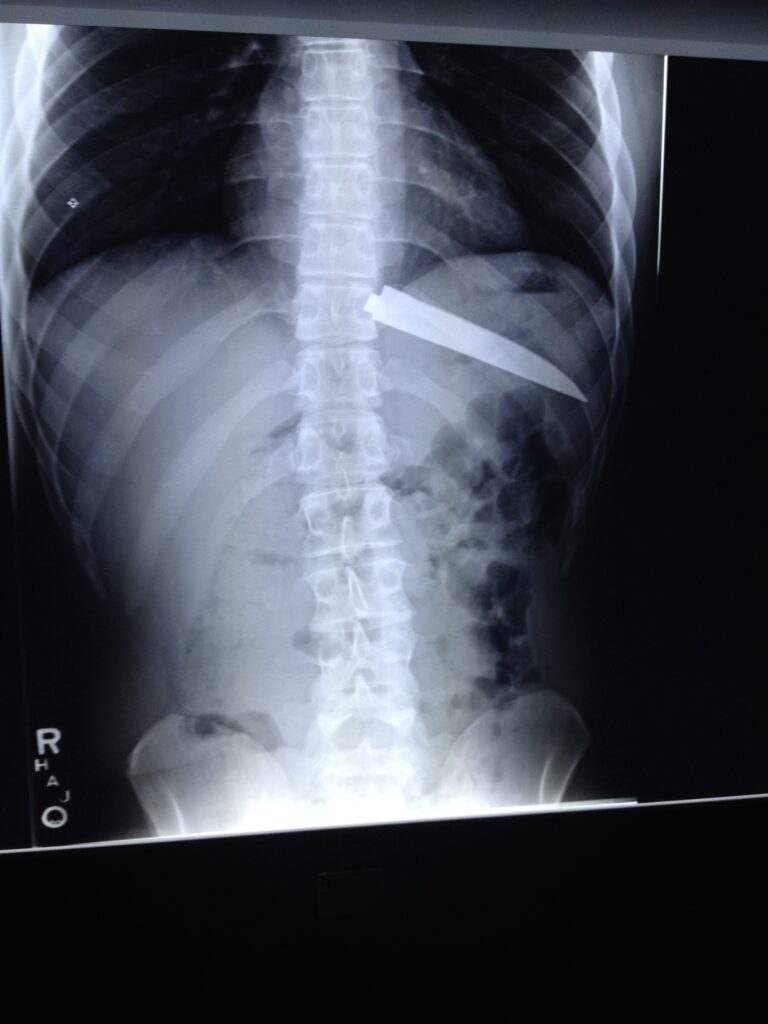

The x-ry of the man who swallowed the knike in the chapter on ‘foreign bodies’

the same knife and the thick tape coating in which it was wrapped